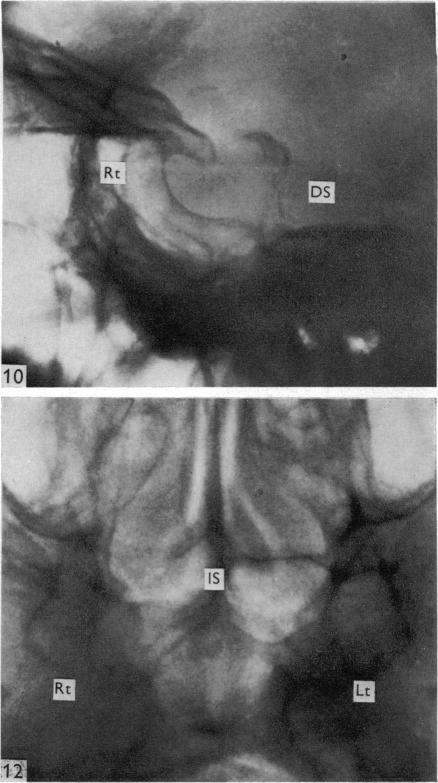

Surgical aspects of the anatomy of the sphenoidal sinuses and the sella turcica.

J Anat. 1977 Dec;124(Pt 3):541-53.